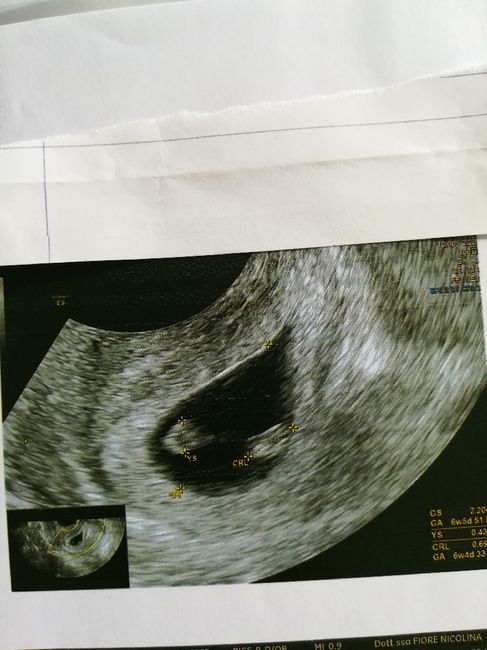

Oggi ho fatto la traslucenza nucale e la dottoressa mi ha detto che il fagiolino era in posizione impeccabile,tanto che il tubercolo si vedeva benissimo e mi ha detto femmina al 100%. Io già da ramzi avevo predetto femmina, ma aspettavo di snetirmelo dire. E così, com'è stato per il primo figlio dove secondo ramzi era maschio, e maschio è stato, anche stavolta ci ha preso 😍 siamo felicissimi, la bimba sta alla grande e si chiamerà VITTORIA. 🌺🌺🌺🌸🌸 Vi lascio l'eco di oggi dove si vede benissimo il tubercolo parallelo alla spina dorsale. Un bacio